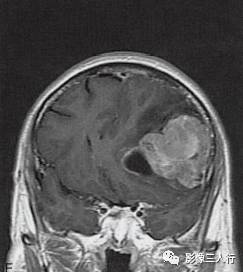

左侧额颞叶多形性胶质母细胞瘤

A.T1WI横断面;B.T2WI横断面;CFLAIR横断面;D.T1WI增强;E.T1WI增强冠状面;F.T1WI增强矢状面;G.HE×40;H.GFAR( )×40

左侧额颞叶见较大不规则囊实性肿块,大小约5.4cm×8.3cm,平扫T1WI呈低信号、T2WI呈高信号(图A、B),肿块内有斑片状囊变区;增强扫描肿块实性部分呈不均匀明显强化,囊性部分呈环形强化(图D~F)。肿块占位效应明显,周围见环形水肿(图C)。